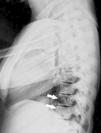

In imaging studies, in addition to marked bone sclerosis, her spine showed the presence of lines parallel to the cortex of the vertebral bodies giving rise to an image of a small copy of the vertebral body within the body, a sign called “bone within a bone” (Figs. 1–3). This sign was evident in several vertebral bodies. Morphometric vertebral deformities showed no calcification of paraspinal ligaments.